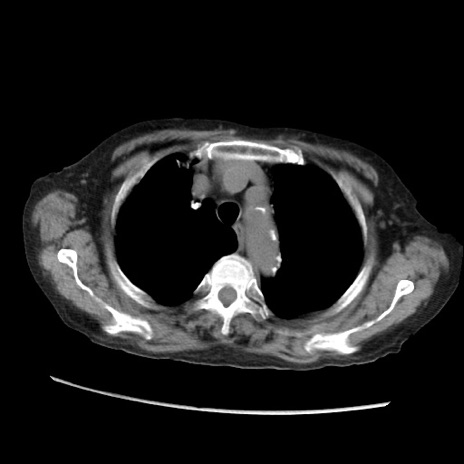

症例31(横断像)

【症例】80歳代 女性

【主訴】腹部膨満感

【現病歴】他院にて肝硬変にてフォロー中。1週間前から便秘、腹部膨満感、臍部腫瘤あり受診となる。

【既往歴】肝硬変

【身体所見】腹部膨隆あり、皮膚変化なし、疼痛なし。

【データ】WBC 4600、CRP 0.25